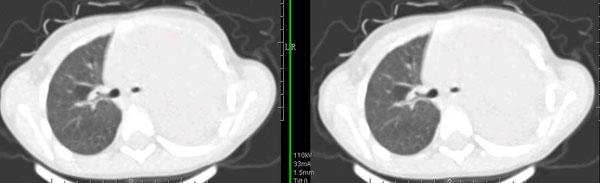

男孩,4岁,发热咳嗽4天。

下面补充ct图片:

此病人是我接手的,发热、咳嗽来做胸透,透视见左侧肺野大部密实,纵隔、心影明显左移,呼吸示纵隔摆动、膈肌矛盾运动(透视下采集了几幅图片),左肺动度明显减弱。询问病人家长,没有吃花生米等呛咳史。由于其影像特征明显,当时诊断:考虑左侧支气管异物并阻塞性肺不张、肺炎。

病人去上级医院支气管镜取出了异物。今天询问上级医院耳鼻喉科主任(是我同学),得知病人异物为胶冻样合并有少许白色粉末,后小儿说晚上喝药片时呛咳过,考虑当时为药片阻塞;另外支气管镜检发现小儿左侧支气管发育略窄,经住院抗炎治疗,现病人基本康复。

多谢各位关注及精彩点评!追踪病人结果时才知道还做过ct检查!对不起!有点晚了,刚刚下载,上传供大家参考!